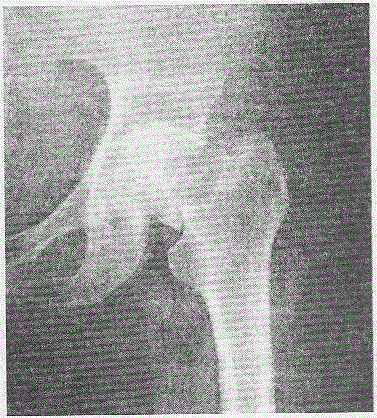

问题 女性,75岁,摔伤致左髋部疼痛、肿胀、活动受限1小时,X线检查如下图所示,断端无明显移位。 急诊手术的最佳时限是

选项 A.6~12小时 B.13~24小时 C.24~48小时 D.1周内 E.骨牵引2周

答案 C